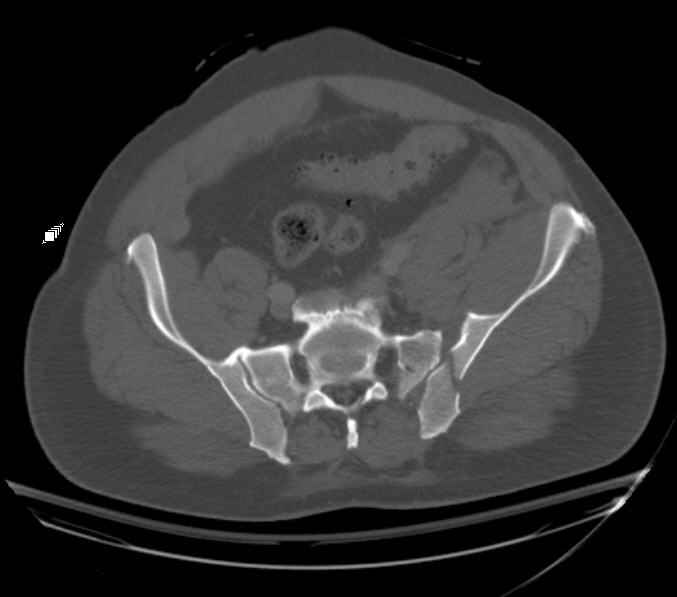

Hello gentlemen- Case is 52 YO male, fell out of treestand while deerhunting. He is 6 ft, approx. 260-275 lbs. Was hemodynamic unstable at local ER, sent to our Trauma center where circumferential pelvic binder placed and pt. stabilized with fluid, blood, and rewarming. Angiography not performed. An extraperitoneal bladder disruption was found, uro elected to treat non-operatively. Initial xray (not shown) demonstrated 5-7 cm wide at symphysis and SI joint. The first image attached is of CT once binder is in place. On post trauma day 5 the pt was taken to OR for ORIF of his iliac wing fracture and SI dislocation. The swelling/3rd spacing of fluid in the area of symphysis was profound, but quite acceptable posteriorly. Patient was prone for procedure, as I thought too difficult to fix the wing in lateral position. Of course the repair of wing was easy, but reduction of SI very demanding. The Floro images document the residual lack of reduction. That was the closest I could get it using 6mm joystick in wing, and clamp on sacrum and clamp through notch. The fixation was (initially) rigid. Anterior ex fix with supra-acetabular pins was placed due to condition of soft tissues, massive "beer-belly" overhanging the crest. Post trauma day ten patient's xray shows failure of posterior construct. Plan was to perform revision orif once soft tissues resolve considerably for full anrterior fixation and posterior fixation. However, while Im away for holiday (on Post trauma day 15), pt is developing septic clinical appearance, and trauma suspects pelvic abcess near symphysis and performs I and D - finds nothing but no primary closure performed. Posterior tissues/incision continue to look healthy. Now is post trauma day 17, pt is still tubed/on dopamine/and wbc still elevated, anterior incision still packed open. Clearly must get to bottom of possible sepsis, but then what? Thanks for you time - sorry for such lengthy clinical description. Thomas Schaller Kalamazoo, Michigan

Request for more images.. Axial and coronal recon (pt in binder.)